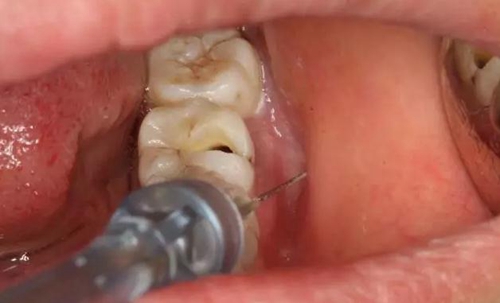

圖3.   取出棉球口內(nèi)發(fā)現(xiàn)37合面有開髓孔,探針出血,頰側(cè)牙齦紅腫。

3.jpg